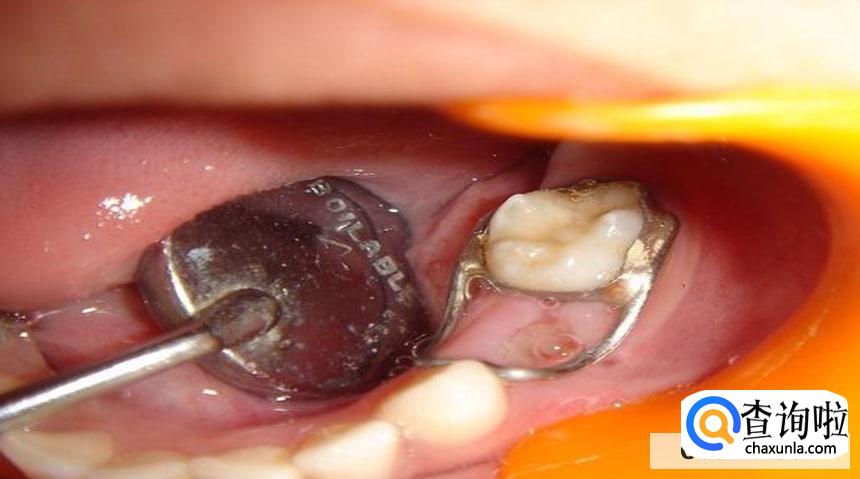

如果说有些小伙伴存在前牙龋洞的时候,应该直接从舌面就开始去腐、备洞,尽量的保留唇侧的牙体结构。但是需要使用复合树脂来进行填充,从而让牙齿恢复美观。

如果说龋齿的洞比较深,遇到冷热刺激的时候,已经出现了特别明显的疼痛。在这个时候应该先安抚镇痛,等到疼痛的症状缓解以后,再进行永久性的填充。

然而小伙伴们在使用复合树脂进行填充的时候,一定要将酸蚀剂彻底的冲洗,然后再涂布粘接剂,避免牙齿出现一些相对敏感的症状。

其实邻面洞填充的时候,首先要去除一些多余的材料,避免在补牙的时候形成了悬突,从而刺激牙龈。